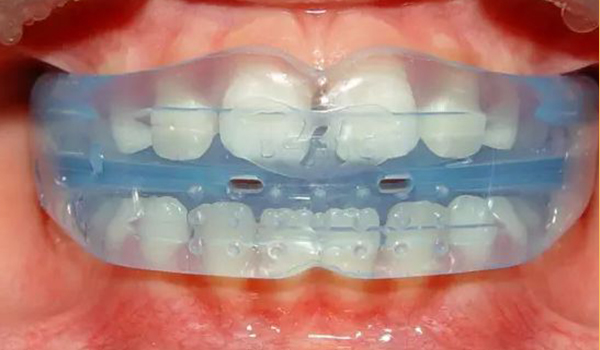

早期矯正

兒童優選 · 專為(wèi)3~12歲兒童設計

量身定制 · 針對孩子不同情況定制矯正計劃

正牙助萌 · 同步完成獲得理(lǐ)想面型